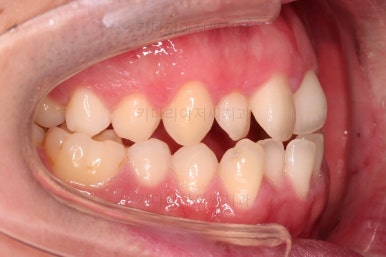

수술 전 교정과정이 거의 마무리 되어 갑니다.

오히려 앞니가 거꾸로 물리는 정도는 더 심해지고요.

수술 직전이 얼굴모습도 가장 주걱턱이 심한 양상으로 됩니다.

농담 삼아 못생겨지면 못생겨질수록 수술이 더 잘될겁니다 라고 말씀 드립니다.